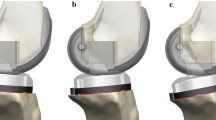

To assess the effect of surgical referencing technique, two series of analyses were designed. In the first series, the tibial slope was altered by rotating the tibial component on the sagittal plane around a pivot point located at the anterior aspect of the proximal tibia (ACR technique, Fig. 2a). With such technique, a more posterior tibial slope would shift distally all the points of the tibial plateau, and a more anterior slope, would shift them proximally. In the second series, the pivot point was defined as the midpoint between the centres of the medial and lateral tibial plateaus (CPR technique, Fig. 2b). In this situation, a more posterior tibial slope would shift distally all the points located posteriorly to the pivot point, and proximally all the points located anteriorly, and vice versa for a more anterior slope. In addition to the neutral slope case (0°), four more cases were analysed, three with more posterior slope (+3°, +6°, +9°) and one with more anterior slope (–3°), with both ACR and CPR technique, leading to five slope cases in each technique.

Schematic representation of a anterior tibial cortex referencing (ACR) and b centre of tibial plateau referencing (CPR) techniques used in this study to alter the tibial slope. The crossed circles represent the pivot point for the virtual resection. The outline of the tibial insert from −3° to +9° of tibial slope is superimposed. With ACR technique a more posterior tibial slope shifts all points on the tibial plateau distally, and a more anterior slope, proximally (a). With CPR technique, changing the degree of tibial slope does not alter the joint line in correspondence of the pivot point (b)